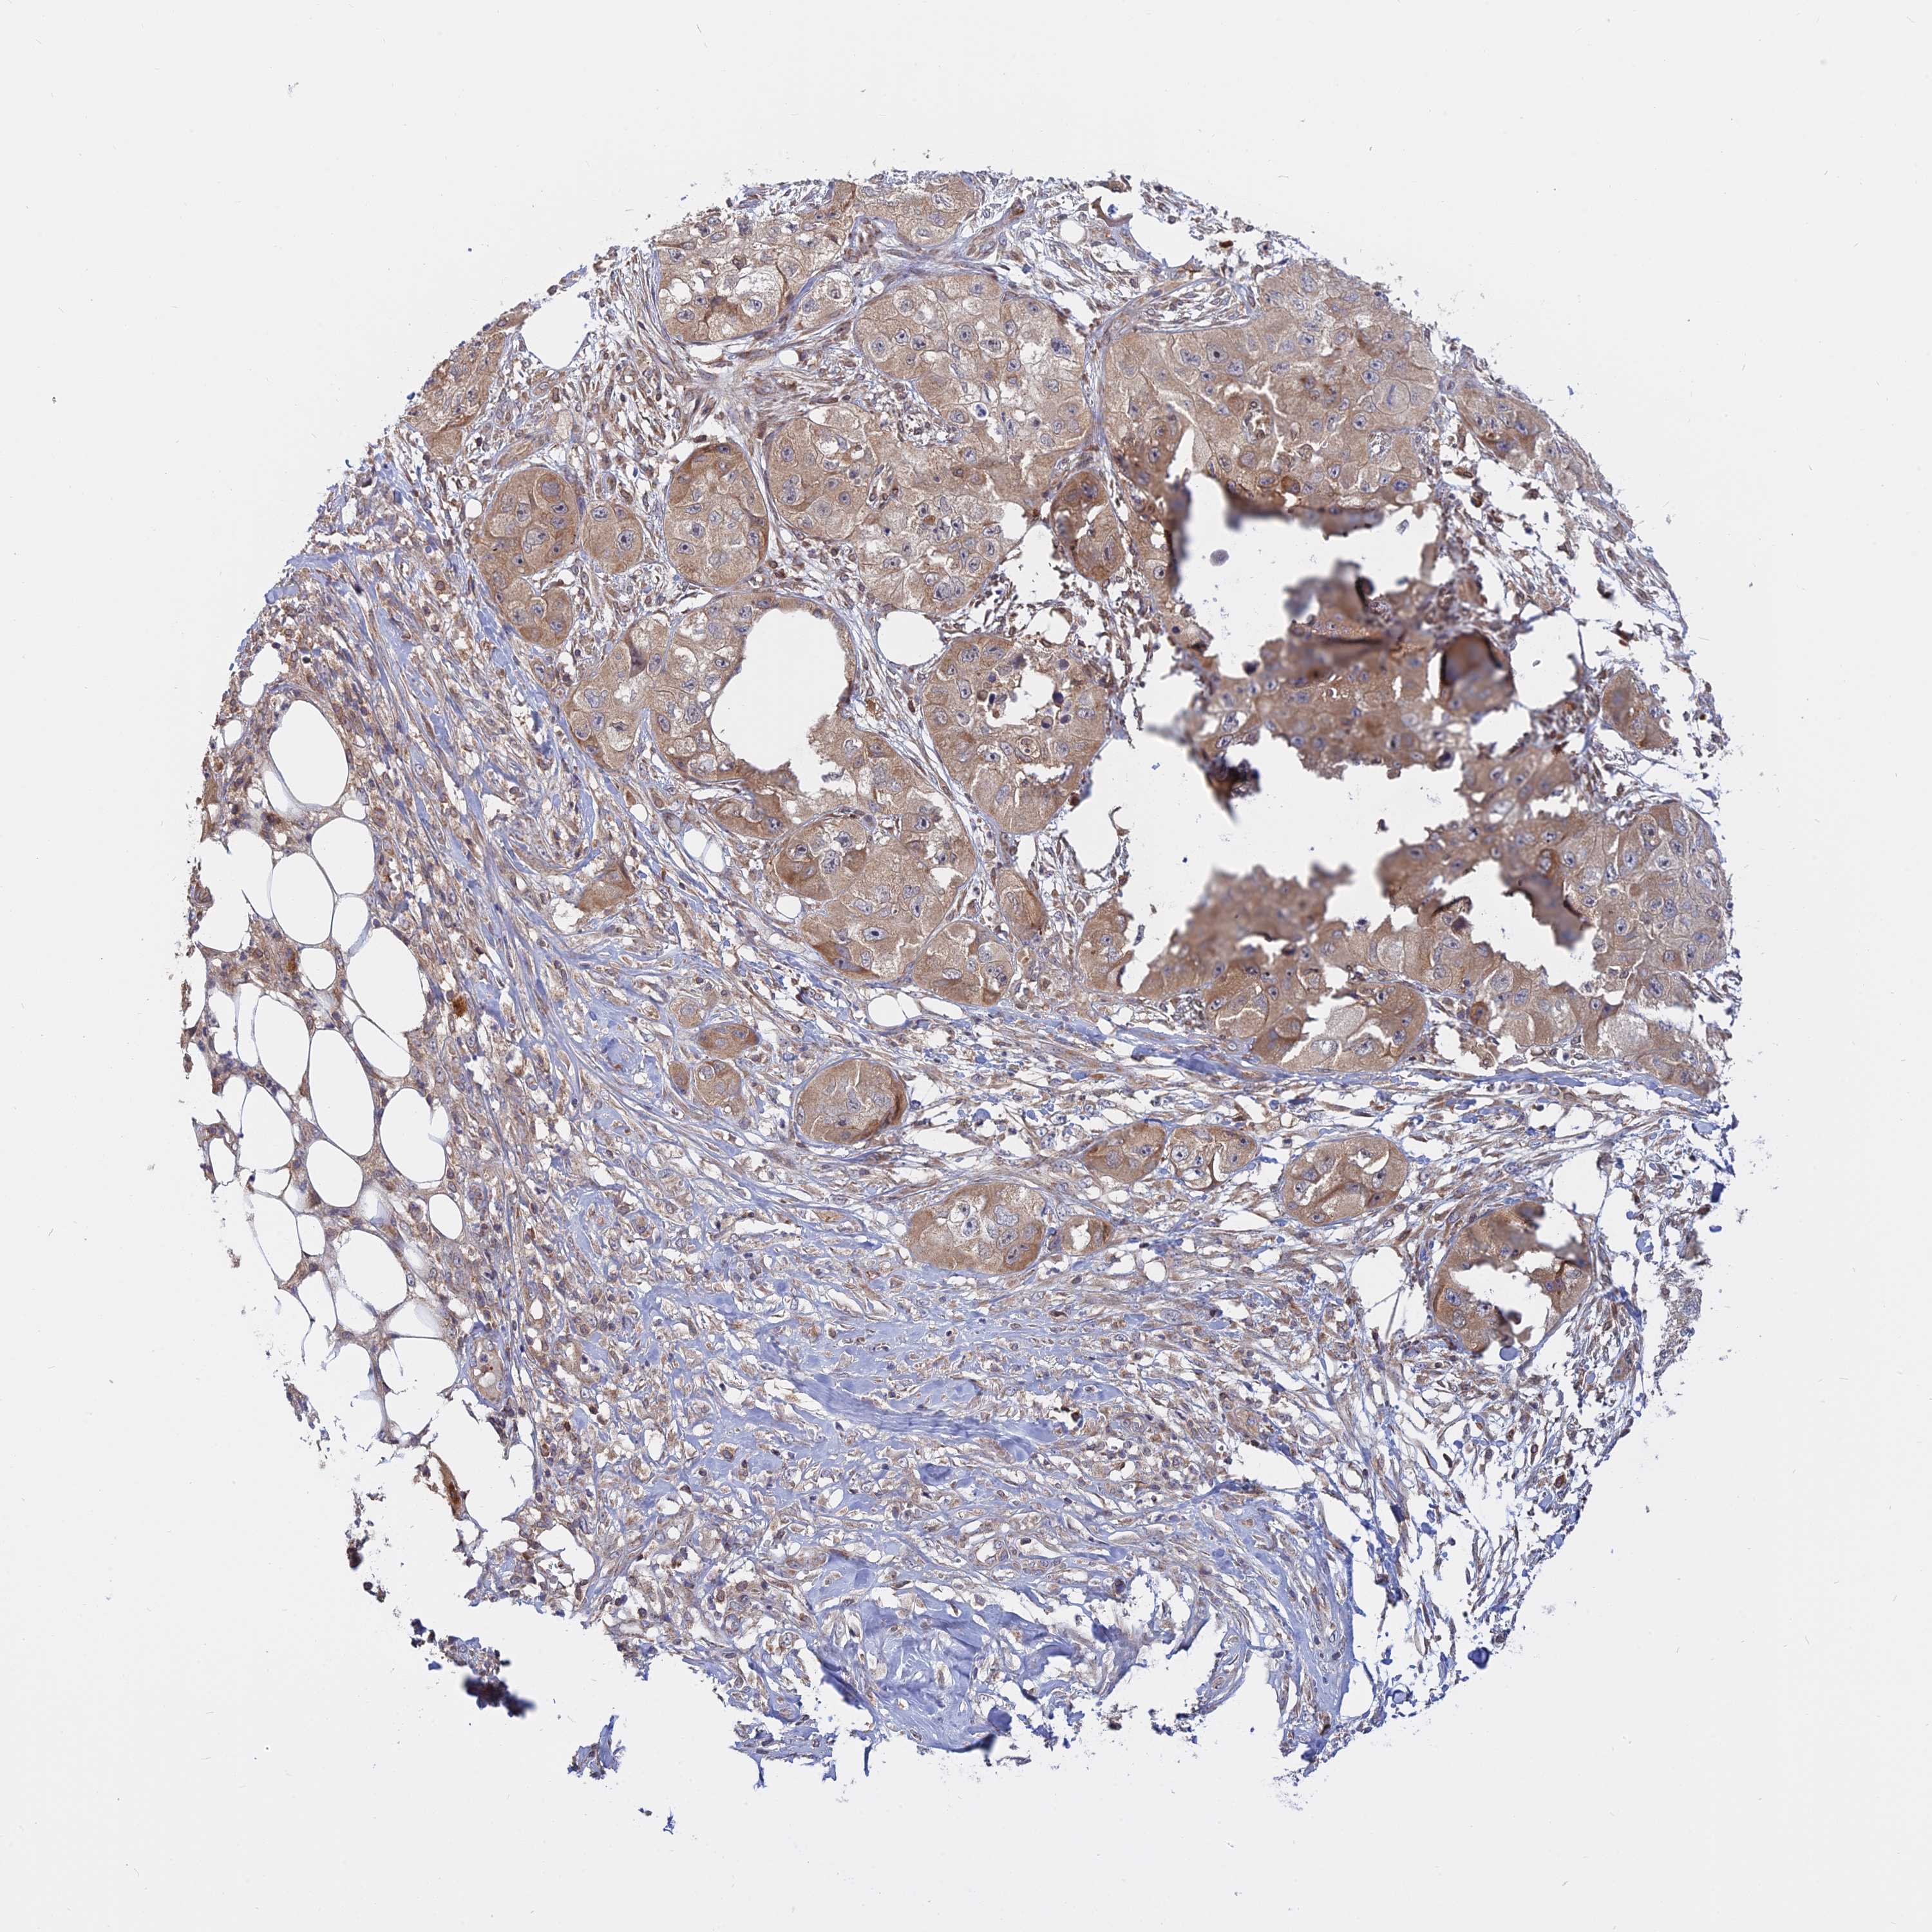

SKIN CANCER - Protein expressioni

A mouse-over function shows sample information and annotation data. Click on an image to view it in a full screen mode. Samples can be filtered based on level of antibody staining by selecting one or several of the following categories: high, medium, low and not detected. The assay and annotation is described here.

Antibody stainingi

Antibody staining in the annotated cell types in the current human tissue is reported as not detected, low, medium, or high, based on conventional immunohistochemistry profiling in selected tissues. This score is based on the combination of the staining intensity and fraction of stained cells.

Each image is clickable and will lead to virtual microscopy that enables deeper exploration of all samples and also displays staining intensity scores, fraction scores and subcellular localization as well as patient and tissue information for each sample.

Antibody HPA042296

Staining

High

Medium

Low

Not detected

Intensity

Strong

Moderate

Weak

Negative

Quantity

>75%

75%-25%

<25%

None

Location

Nuclear

Cytoplasmic/membranous

Cytoplasmic/membranous,nuclear

Squamous cell carcinoma, metastatic, NOS

Squamous cell carcinoma, NOS